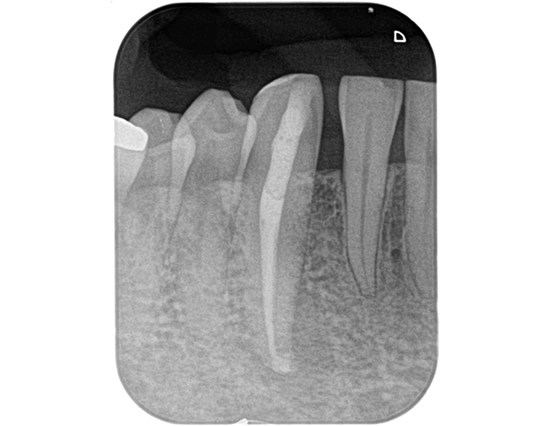

根管治療 症例7

治療後